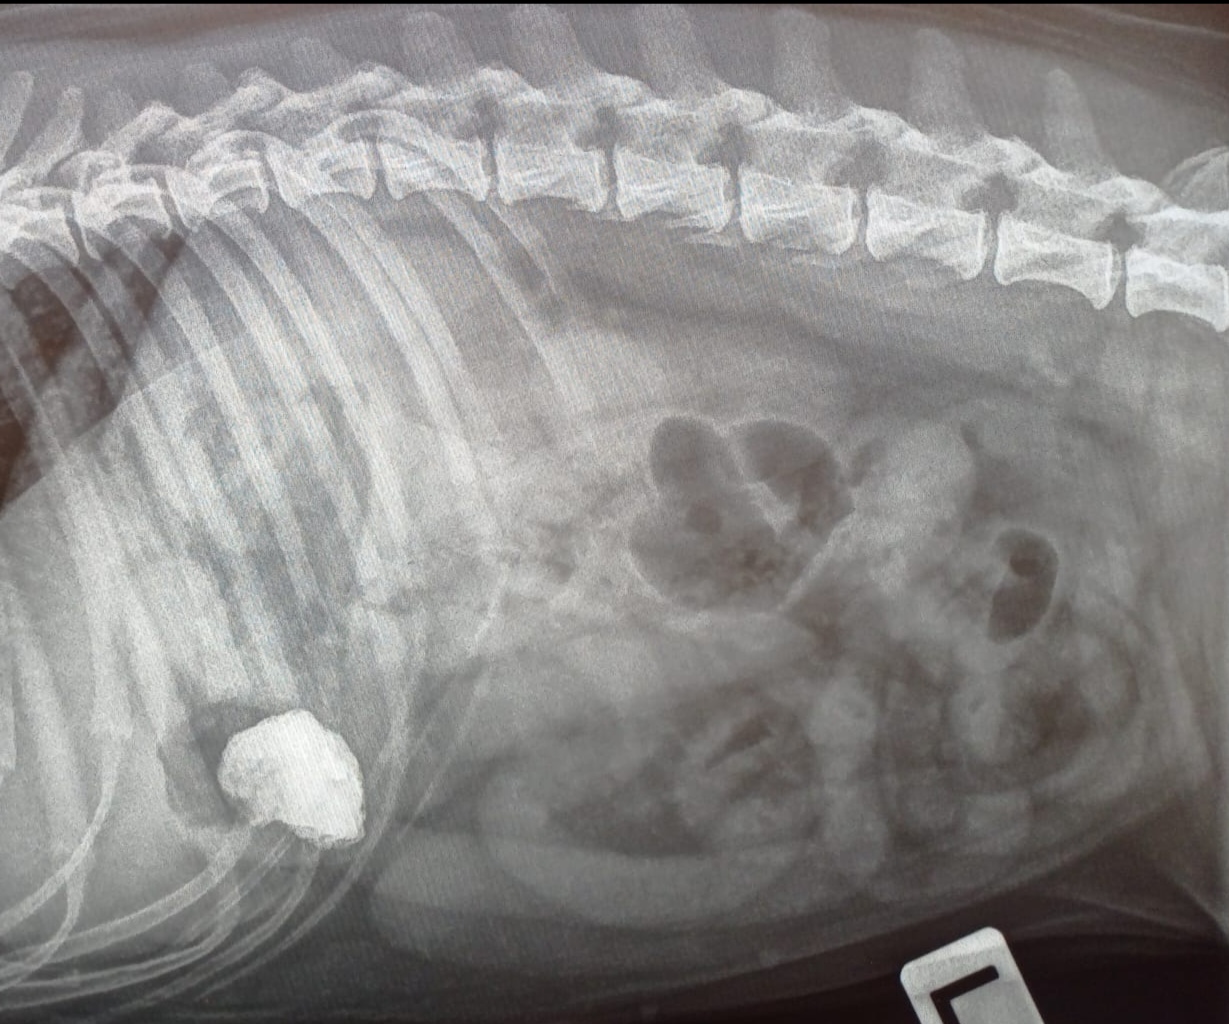

Kuukauden Leikkauspotilas: Koiran mahalaukun vierasesine